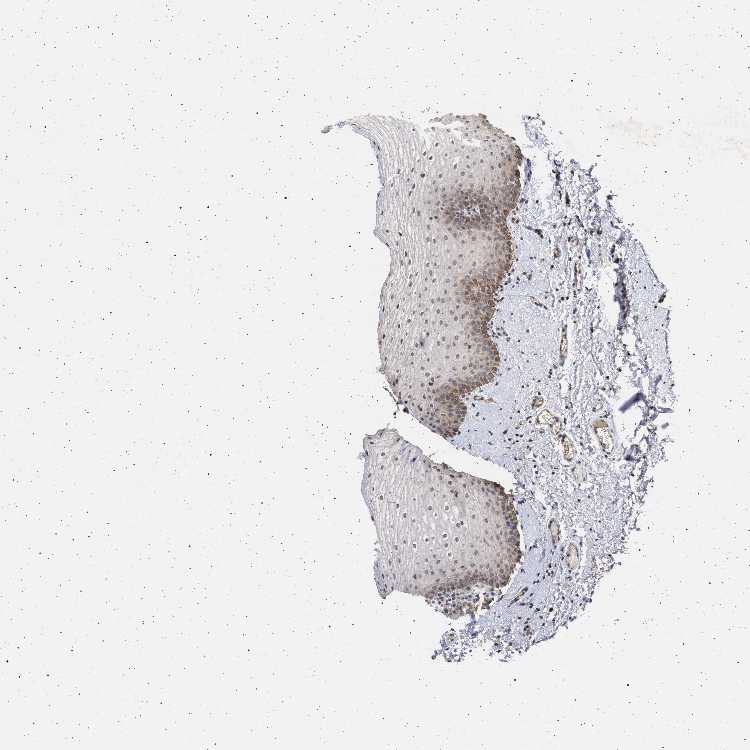

TISSUE PRIMARY DATA ORAL MUCOSA Show tissue menu

ORAL MUCOSA - Antibody stainingi

Antibody staining in the annotated cell types in the current human tissue is reported as not detected, low, medium, or high, based on conventional immunohistochemistry profiling in selected tissues. This score is based on the combination of the staining intensity and fraction of stained cells.

Each image is clickable and will lead to virtual microscopy that enables deeper exploration of all samples and also displays staining intensity scores, fraction scores and subcellular localization as well as patient and tissue information for each sample.

Antibody HPA021410

Squamous epithelial cells Low